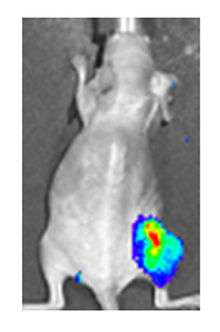

Both in the laboratory and in the clinic it is useful to have a simple means of identifying cells infected by the experimental virus. This can be done by equipping the virus with 'reporter genes' not normally present in viral genomes, which encode easily identifiable protein markers. One example of such proteins is GFP (Green fluorescent protein) which, when present in infected cells, will cause a fluorescent green light to be emitted when stimulated by blue light.[70][71] An advantage of this method is that it can be used on live cells and in patients with superficial infected lesions, it enables rapid non-invasive confirmation of viral infection.[72] Another example of a visual marker useful in living cells is luciferase, an enzyme from the firefly which in the presence of luciferin, emits light detectable by specialized cameras.[70]

Addition of the sodium-iodide symporter (NIS) gene to the viral genome causes infected tumour cells to express NIS and accumulate iodine. When combined with radioiodine therapy it allows local radiotherapy of the tumour, as used to treat thyroid cancer. The radioiodine can also be used to visualise viral replication within the body by the use of a gamma camera.[70] This approach has been used successfully preclinically with adenovirus, measles virus and vaccinia virus.[77][78][79]